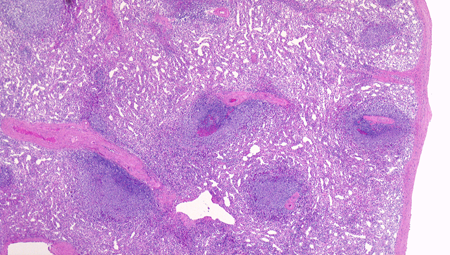

脾臓の組織所見

赤脾髄の構造 Structure of the red pulp

白脾髄の構造 Structure of the white pulp